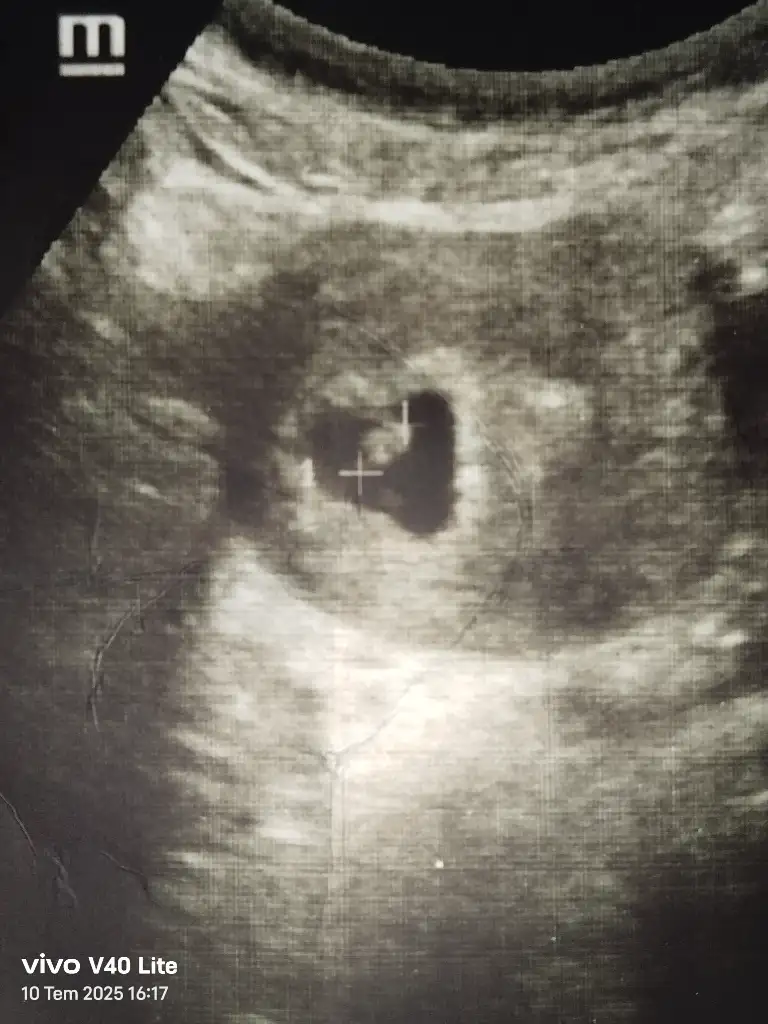

Gözünüz aydın sağlıkla kucağınıza almakta nasip olsunCinsiyet tahmini yapabilden var mı aranızda bugün kalp atışı da duyduk bebişi de gördük 6 hafta 4 günlük

Bence erkek bebek tamamen hissiyatCinsiyet tahmini yapabilden var mı aranızda bugün kalp atışı da duyduk bebişi de gördük 6 hafta 4 günlük